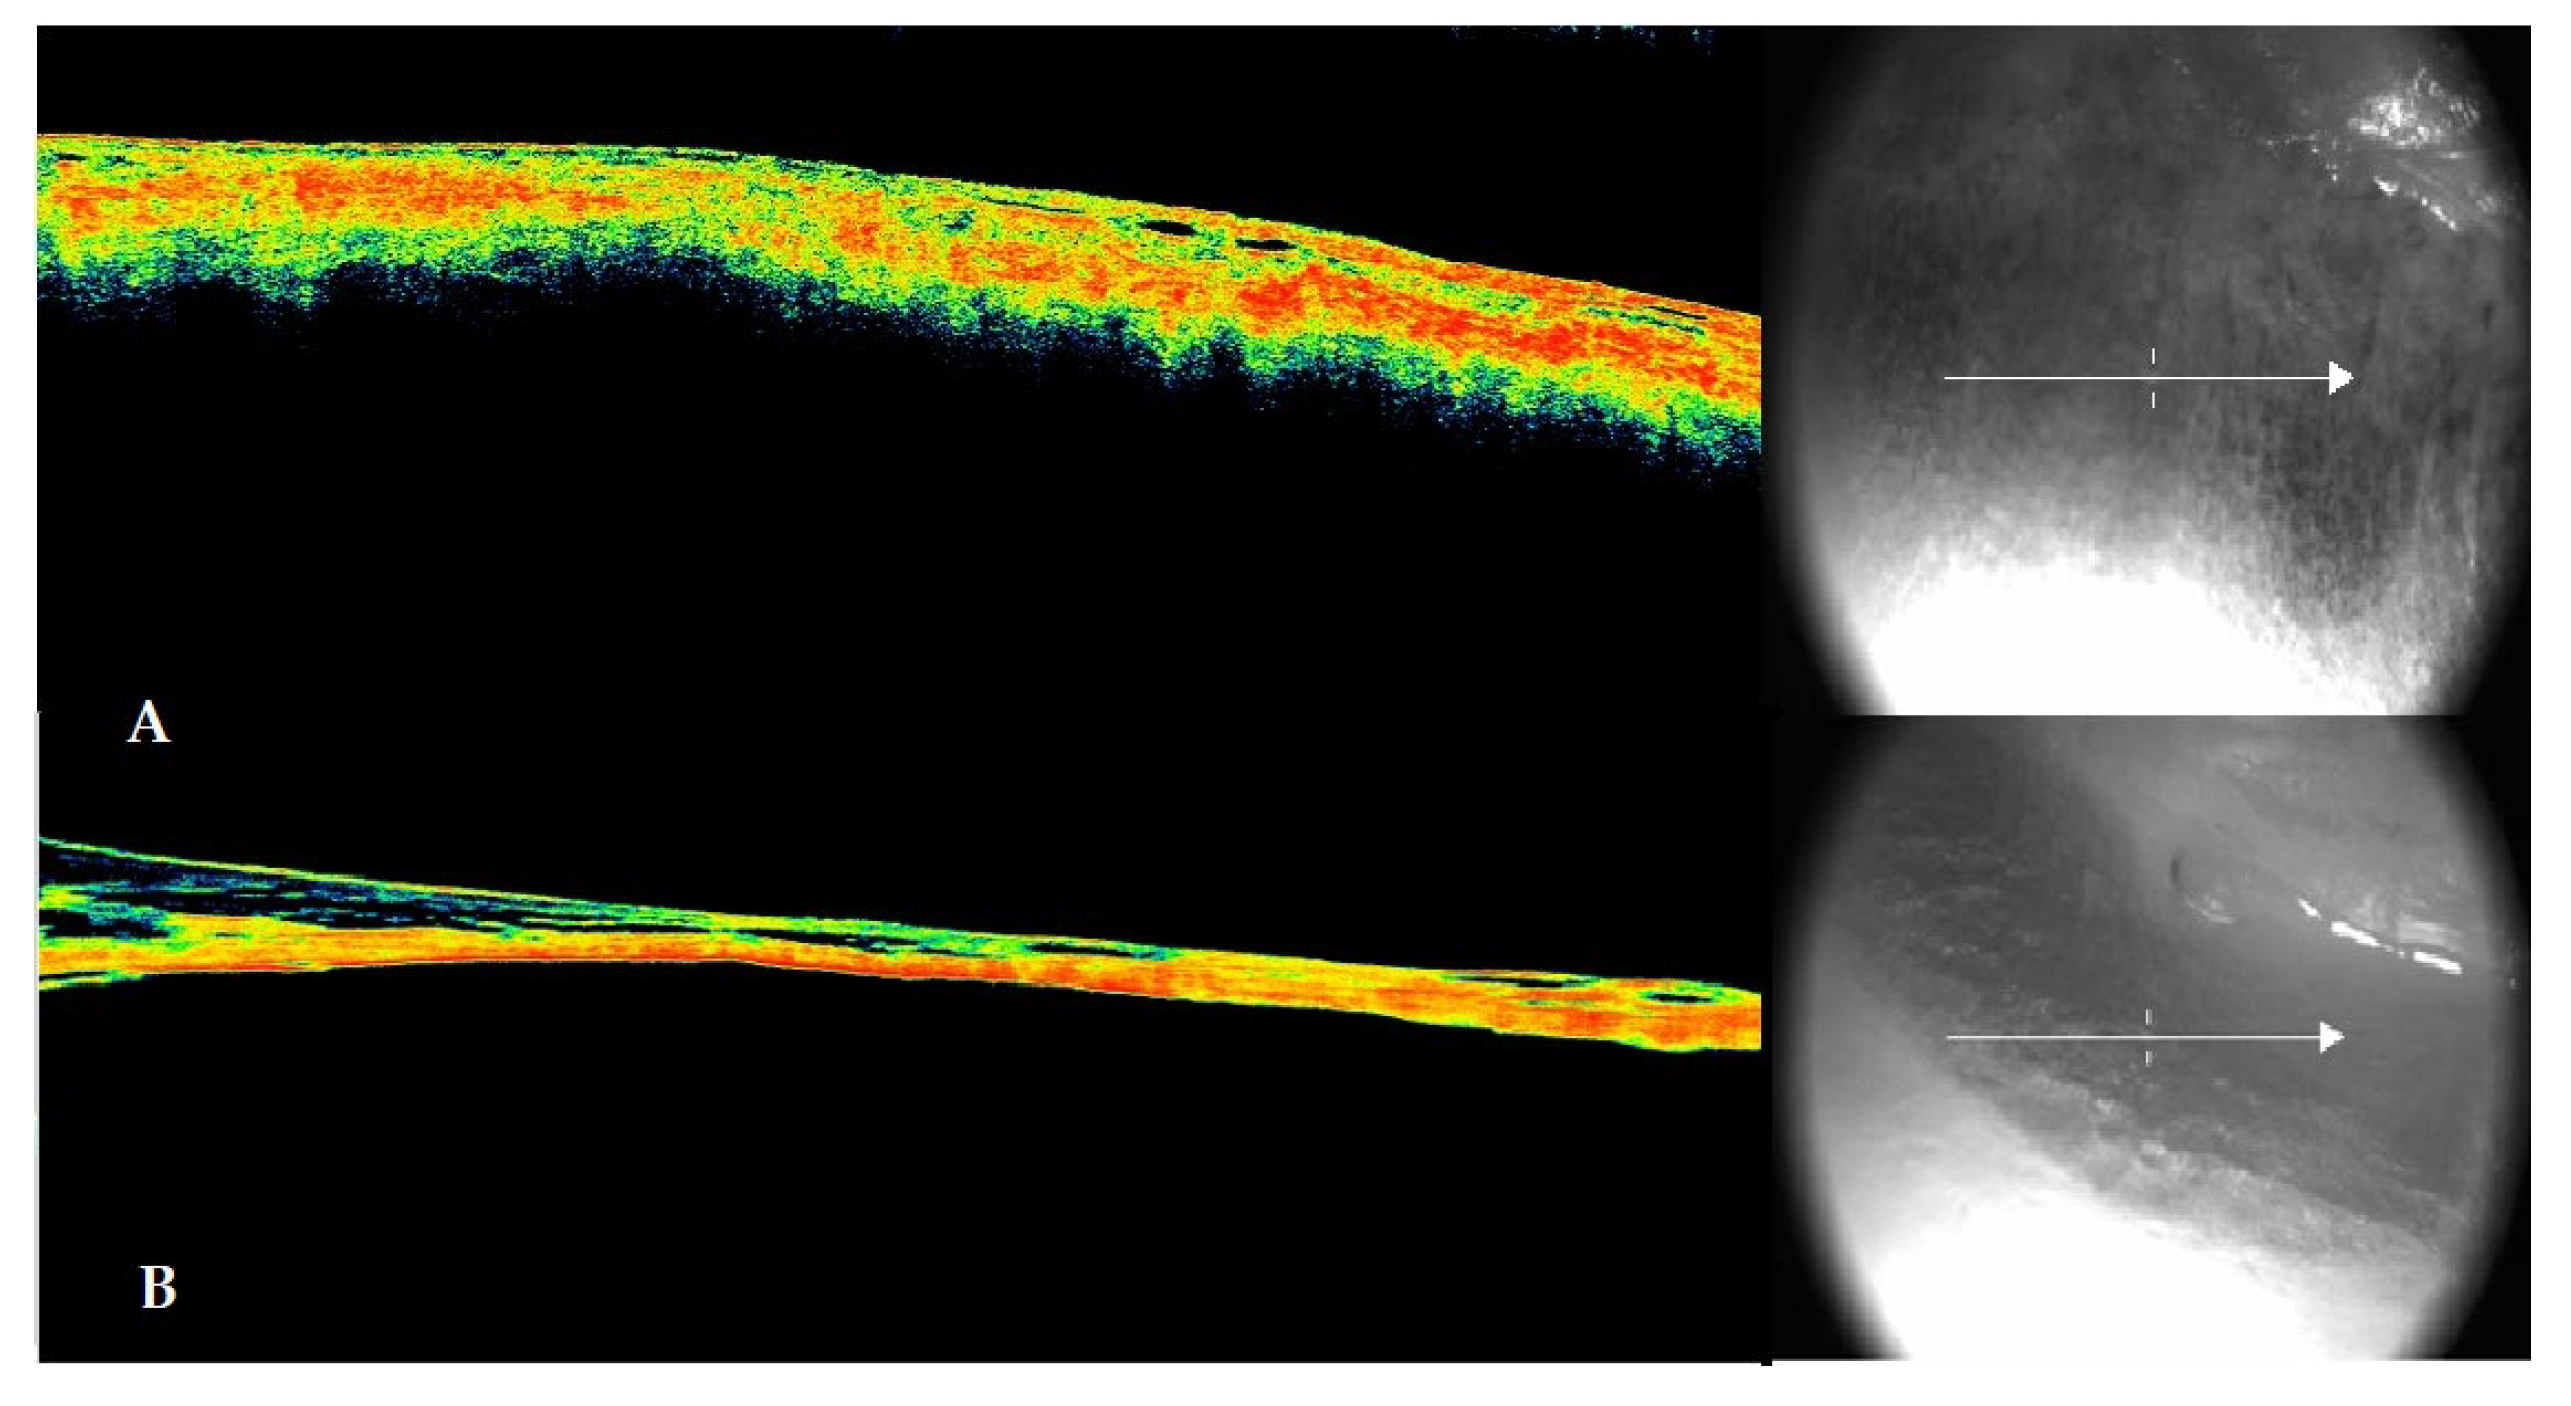

At the first detection of discoloration on the scleral surface, an OCT scan of the structure was performed. The data showed in 100% of early observations, consistent with previous studies, a morphology characterized by the detachment between the scleral layer and the choroid. In the later stages, when the sign was fully manifested, the choroidal detachment was associated with significant dehydration of the sclera, accompanied in all cases by delamination of this structure.

Figure 2. The figure shows in panel A the morphological configuration of the scleral discoloration highlighted through OCT (left side) and the corresponding section (right side). A detachment between the sclera and choroid and initial dehydration of the ocular surface are evident. In panel B, the OCT scan configuration of the dark brown to blackish scleral spot that appeared in the later post-mortem intervals is shown. Both the advanced dehydration of the ocular surface and the clear detachment between the sclera and vitreous (which appears less dense due to probable liquefaction) are evident. The sclera appears delaminated at several points in the inner layers of the tunic.